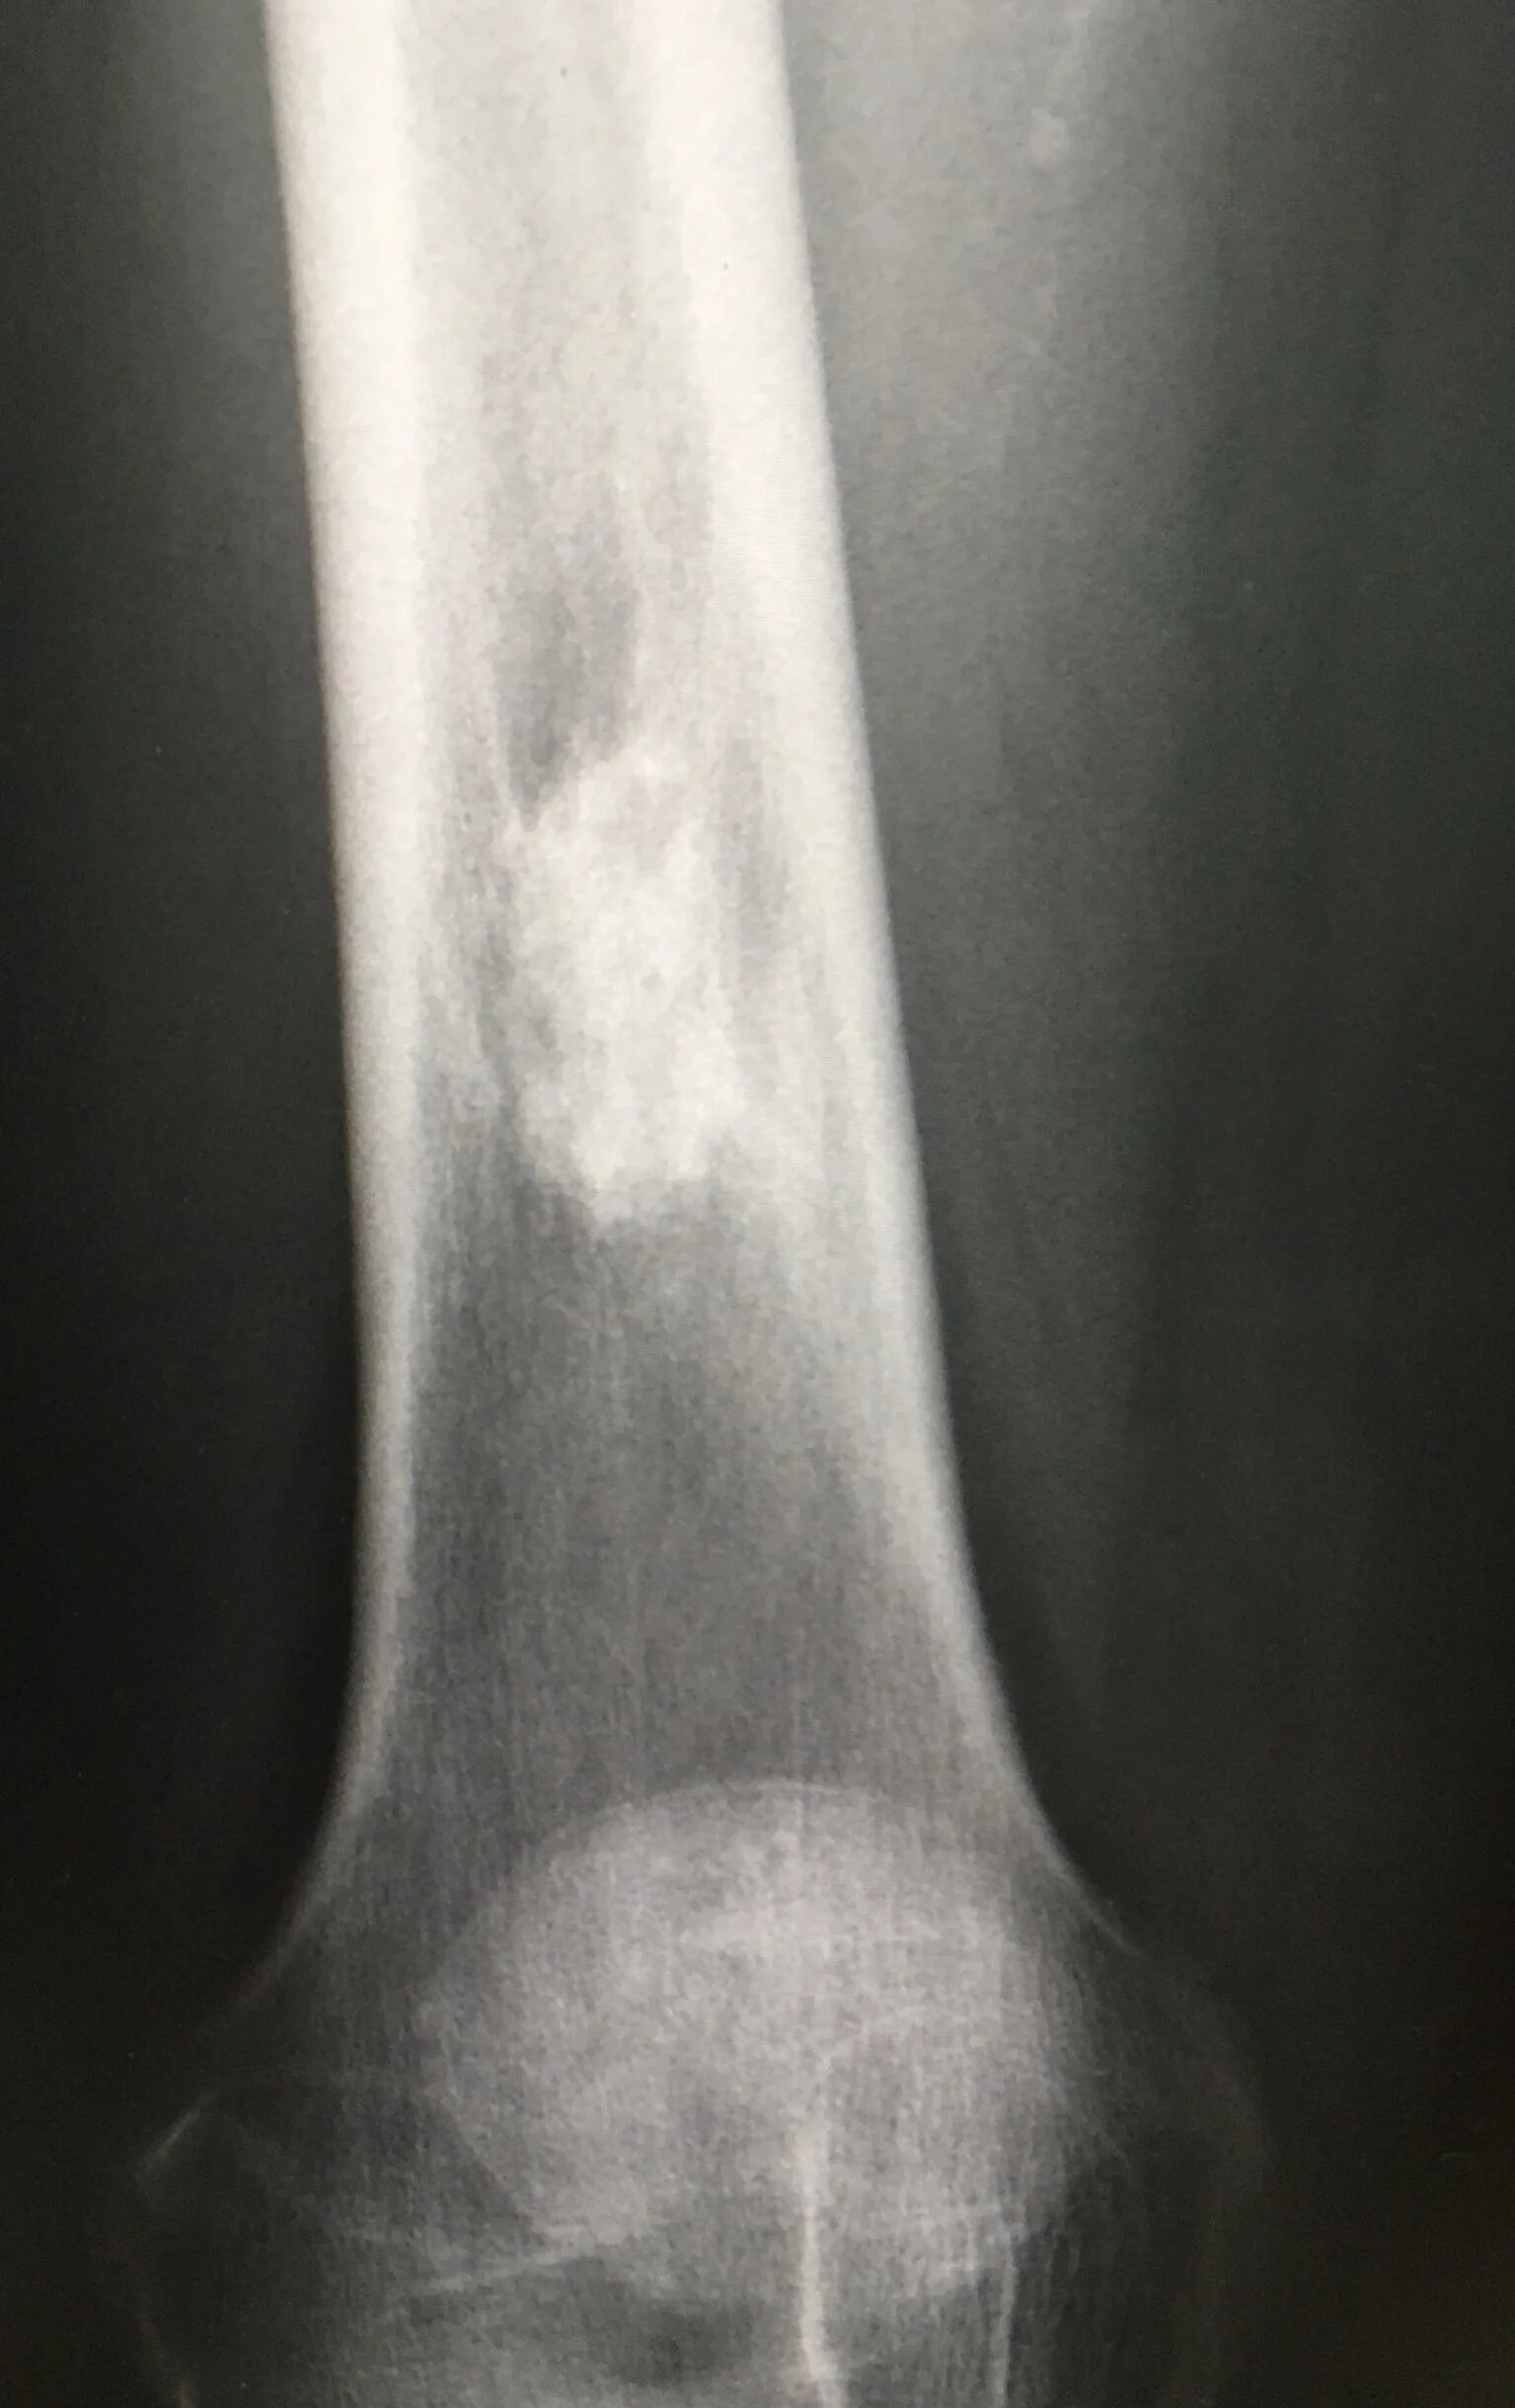

Обызвествление сухожилий мышц